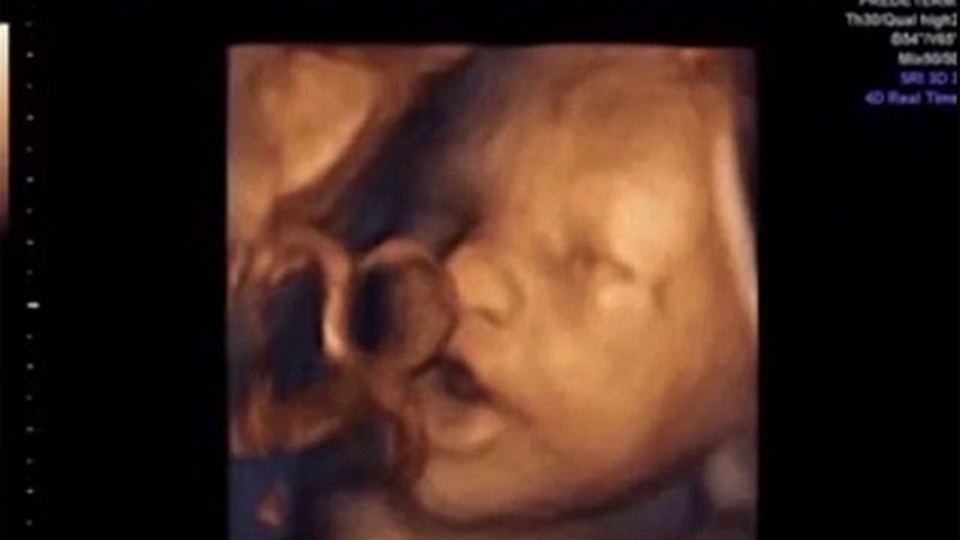

Haberler Yaşam Anne karnındaki bebekler müzik sesine tepki verdi!

Bebekler annelerinin karnındayken tam 16 hafta sonra sesleri duyabiliyor. 14.39 haftalık hamileler üzerinde yapılan çalışmaya göre vajina içine yerleştirilen cihazla bebeklere müzik dinletildi.

Fetüslerden %87'sinin bu seslere tepki verdiği kaydedildi. Bebekleri verdiği tepkilerse videoyu izleyenleri gülümsetiyor.